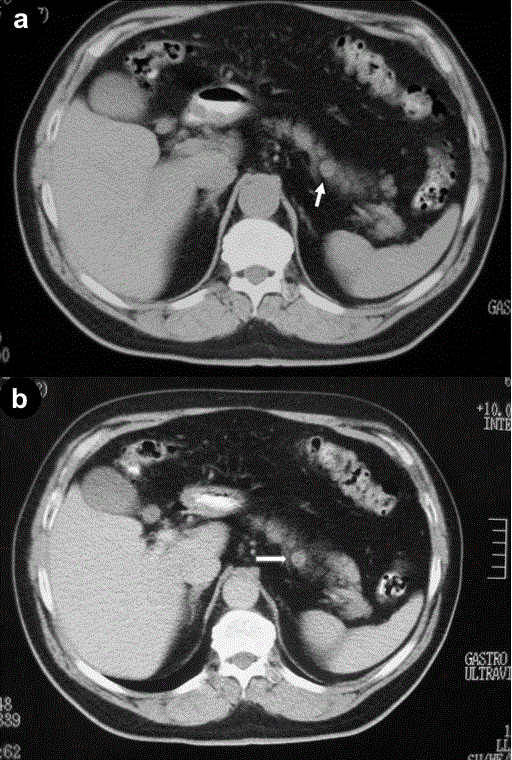

Figure 1. Post contrast CT depicting a small enhancing lesion in the body of the pancreas. Arrows show the lesion.